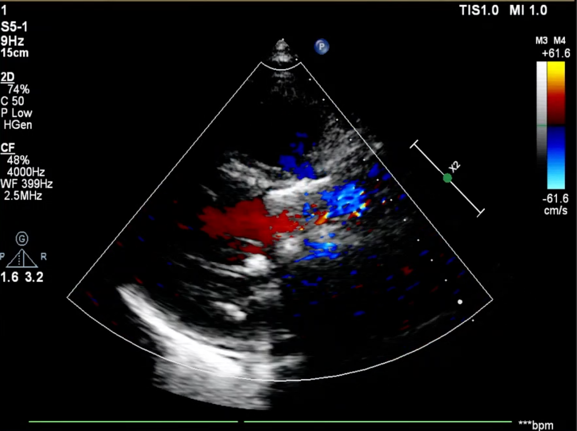

患者为76岁女性,术前超声心动图提示主动脉瓣重度狭窄并轻度关闭不全、峰值流速 5.1m/s、平均跨瓣压差 71mmHg、有效瓣口面积 0.32cm²;双房增大,升主动脉瘤样扩张,左室后壁增厚;二尖瓣轻度反流、三尖瓣中度反流;LVEDd:49mm,LVEF:29%,左心功能减退。

血流动力学改善,瓣膜形态良好,少量瓣周漏